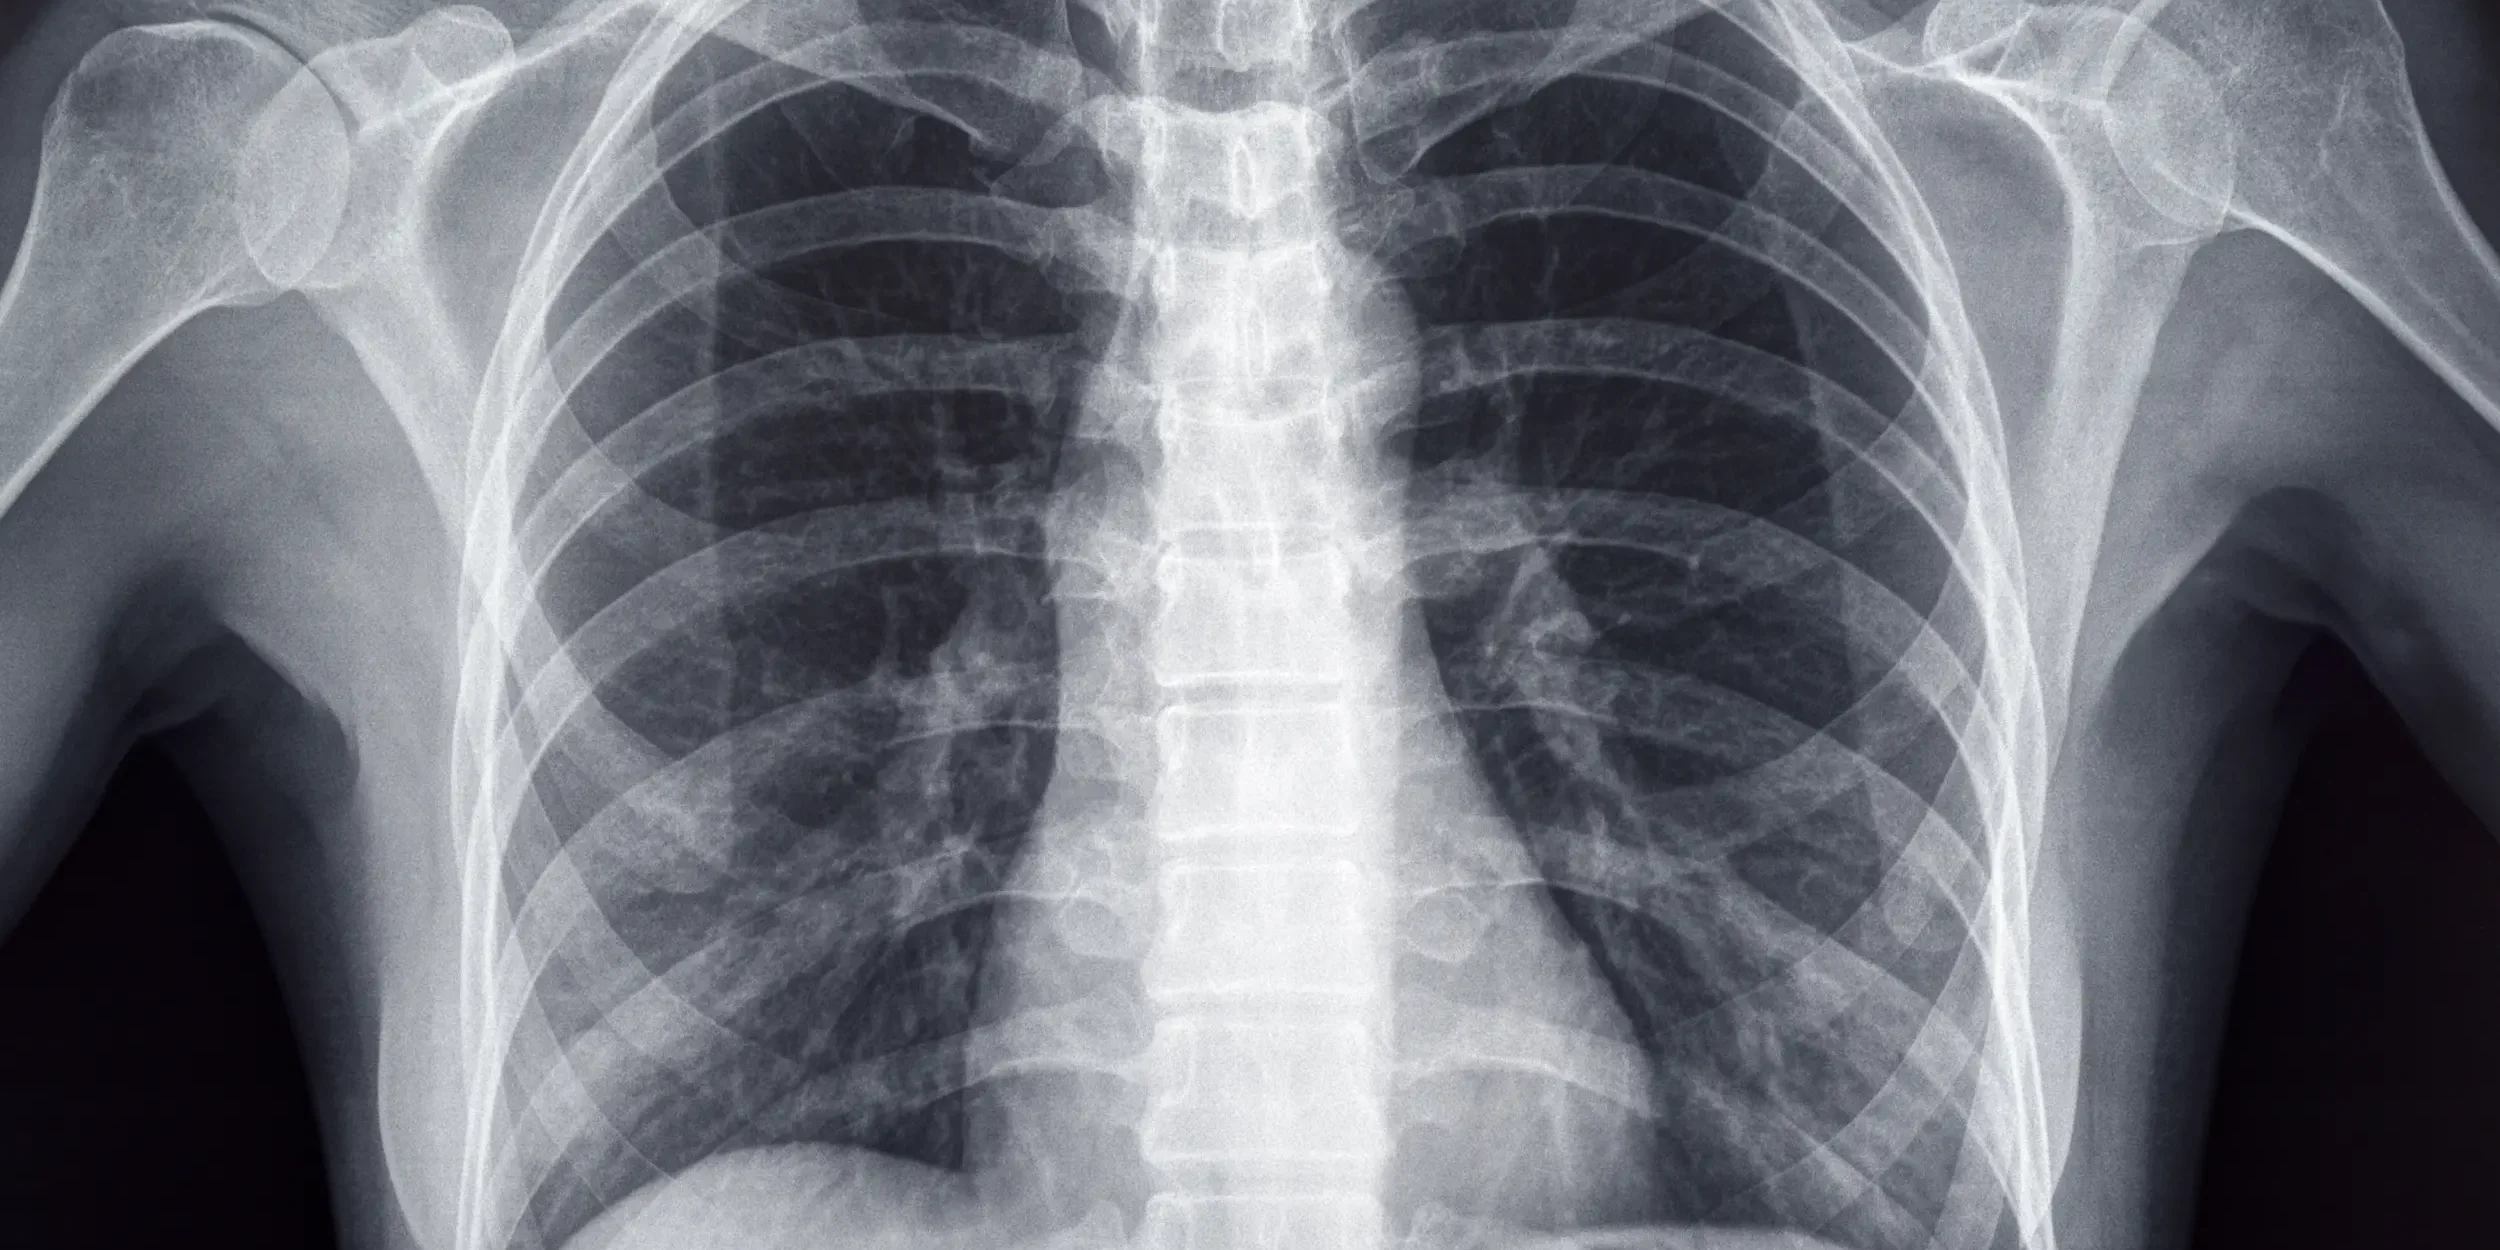

Bone mineral density (BMD) testing is used to evaluate bone strength and the risk of fracture. BMD is measured using specialised imaging techniques, the most common of which is dual-energy X-ray absorptiometry (DEXA or DXA).² This scan measures the amount of minerals, primarily calcium, present in the bones and compares it to reference values for healthy adults.

BMD testing is generally recommended when a risk to bone health is identified. This may include individuals who have experienced a fracture, have a family history of osteoporosis, are postmenopausal or have other risk factors for bone loss.³ The results help healthcare professionals determine whether interventions such as dietary changes, lifestyle adjustments or supplements are required.²

Although BMD testing is not typically performed as part of routine blood work, it provides a more direct assessment of skeletal mineral stores compared to circulating blood levels³. Doctors may recommend a BMD test if blood results are inconclusive or if a patient is experiencing symptoms that suggest a mineral deficiency, such as bone pain or increased fracture risk. Combining BMD testing with regular monitoring of dietary intake and blood nutrient levels ensures a comprehensive approach to maintaining bone health.